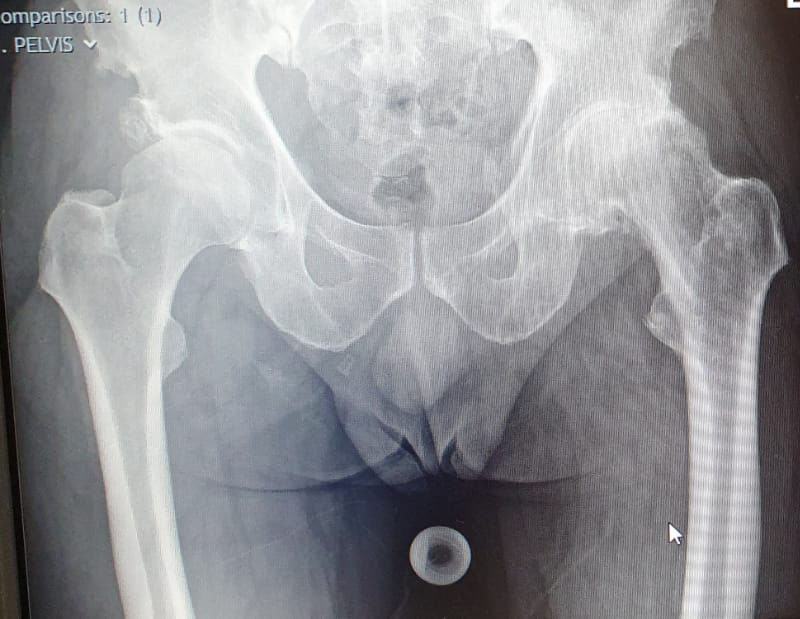

See below for some before and after X-rays of total hip replacement surgeries I have performed to treat Osteoarthritis. Drag the sliders to switch between the before and after images.